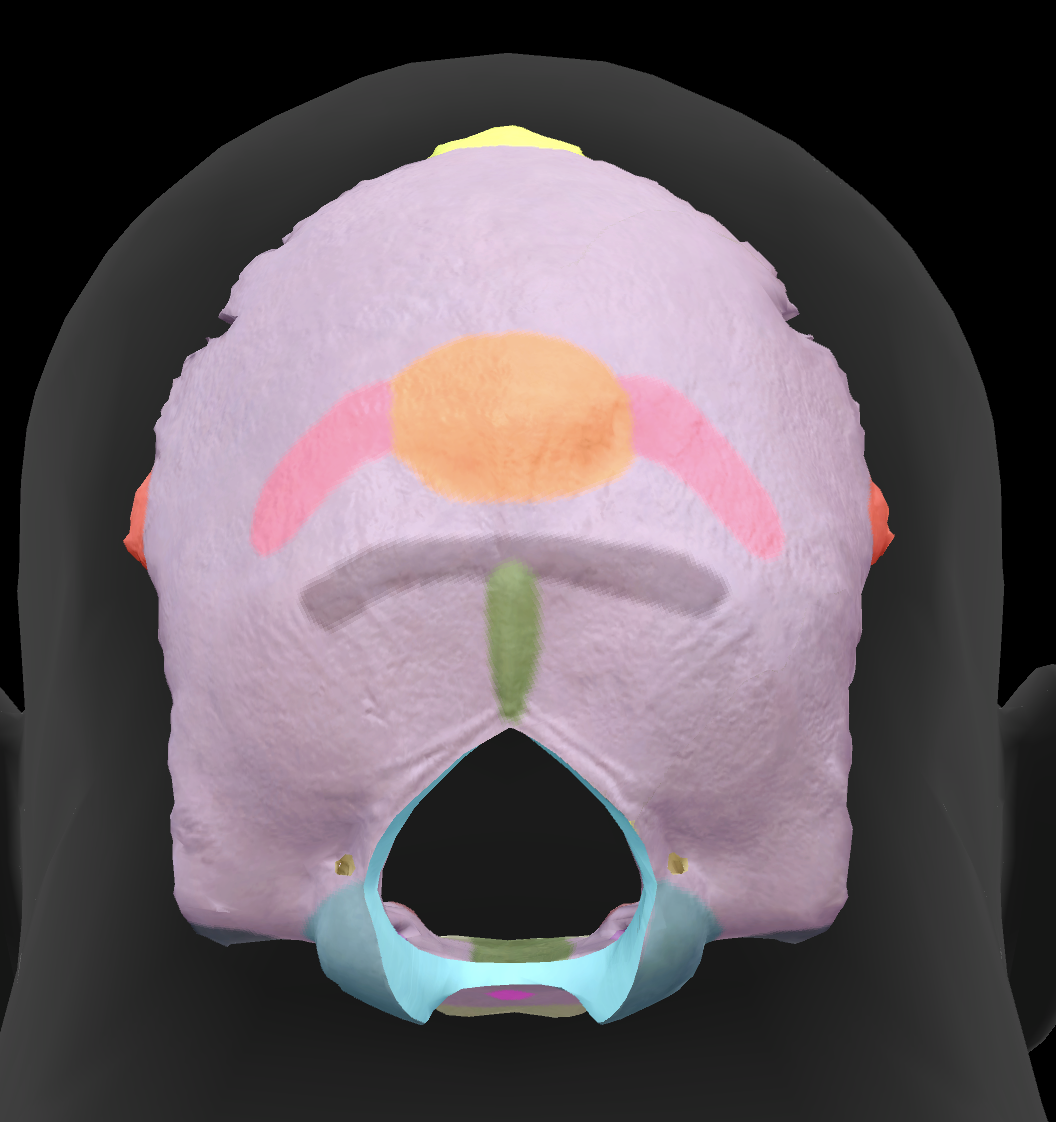

What is the name of this feature?

external occipital protuberance

What is the name of this feature?

superior nuchal line

What is the name of this feature?

inferior nuchal line

What is the hole called?

foramen magnum

What is the name of this feature?

occipital condyles